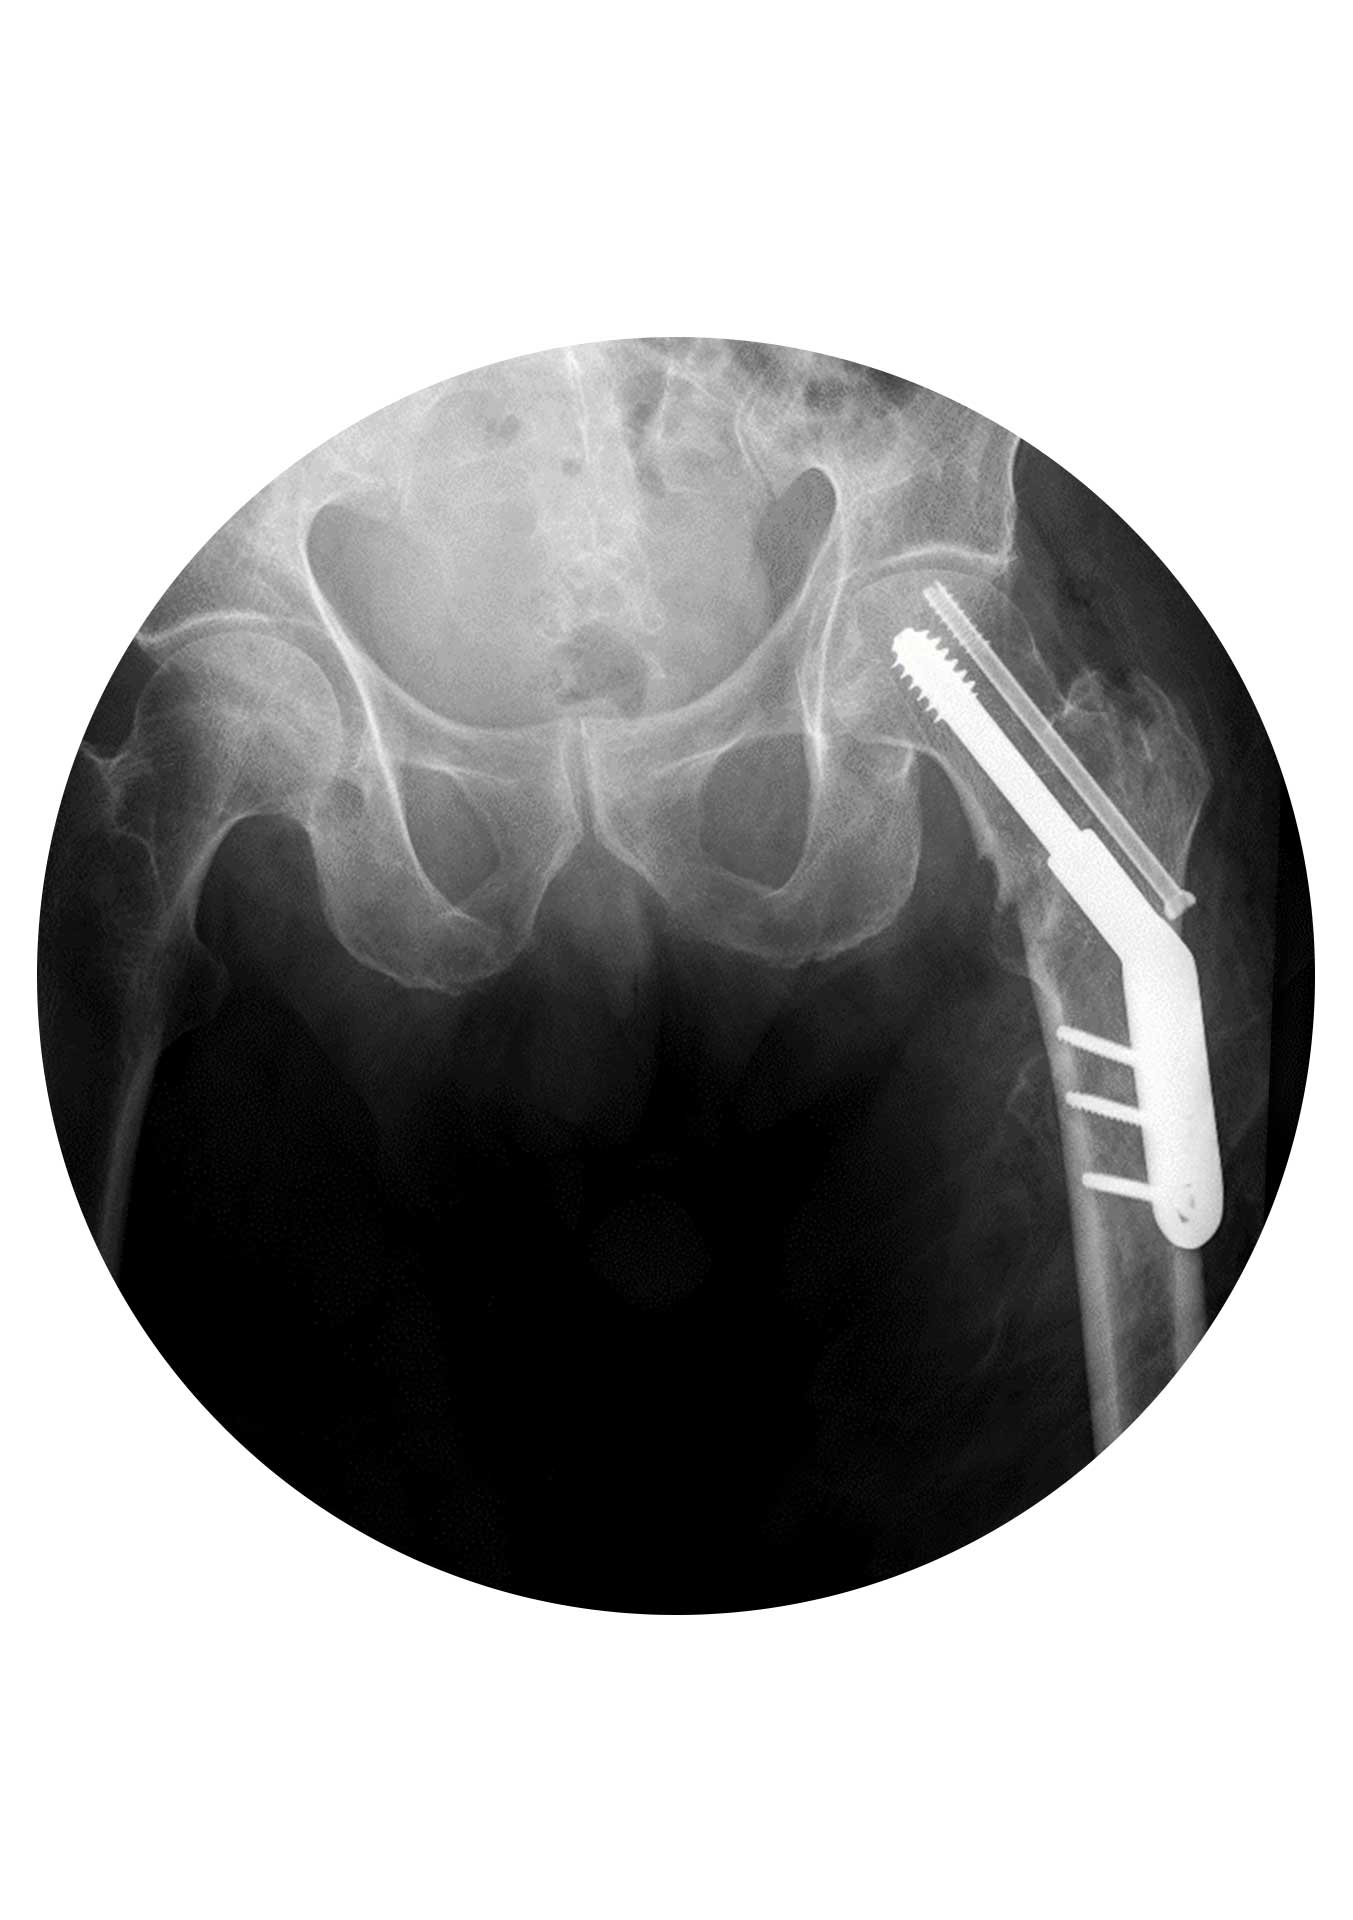

Osteosynthesis of the femoral neck consists of fixing the fracture with screws or plate and screw system in order to allow subsequent bone healing. It is the surgery of choice for fractures without deviation or fractures with deviation in young individuals. It maintains the native hip, avoiding prosthetic joint replacement. It depends, postoperatively, on the type and quality of reduction as well as on the individual’s bone biology, since stabilization of the fracture is not in itself synonymous with consolidation.